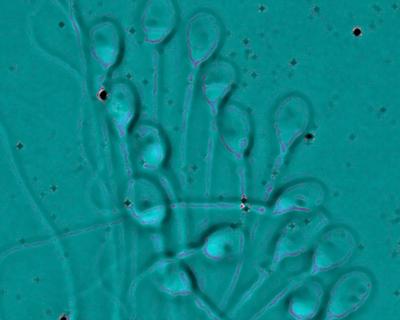

Η μέθοδος επιλογής σπέρματος περιλαμβάνει την μορφολογική εξέταση του σπέρματος με υψηλής ανάλυσης μικροσκόπιο περίπου 5 φορές καλύτερο από αυτό που χρησιμοποιείται έως τώρα.

Με τον τρόπο αυτό, επιλέγονται τα σπερματοζωάρια των οποίων το σχήμα και το μέγεθος υποδηλώνει καλή γενετική ποιότητα κατι που απαιτεί εξειδικευμένη εκπαίδευση για τους εμβρυολόγους. Στη συνέχεια, τα σπερματοζωάρια εμφυτεύονται μέσα στα ωάρια με τη μέθοδο ICSI.